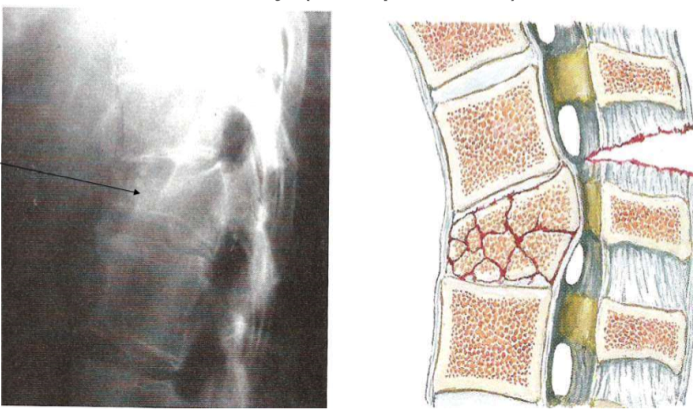

How can osteoporosis affect the vertebra?

This can lead to compression fractures that can trap spinal nerves. This can lead to loss of function or pain. Vertebral compression fractures affect up to 25% of postmenopausal women in the US.

What are these images of?

Vertebral body compression fractures